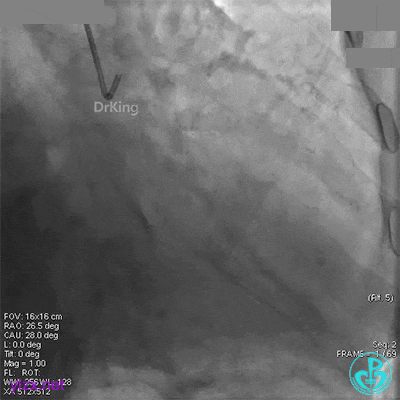

XB 3.0指引导管到位,导丝通过闭塞段至回旋支远段。

另一导丝保护分支,1.5×15mm球囊扩张闭塞处后造影,前向血流缓慢,远端分支血管没有充分显影。

1.5×15mm球囊扩张后前向血流缓慢的原因要高度怀疑慢血流。